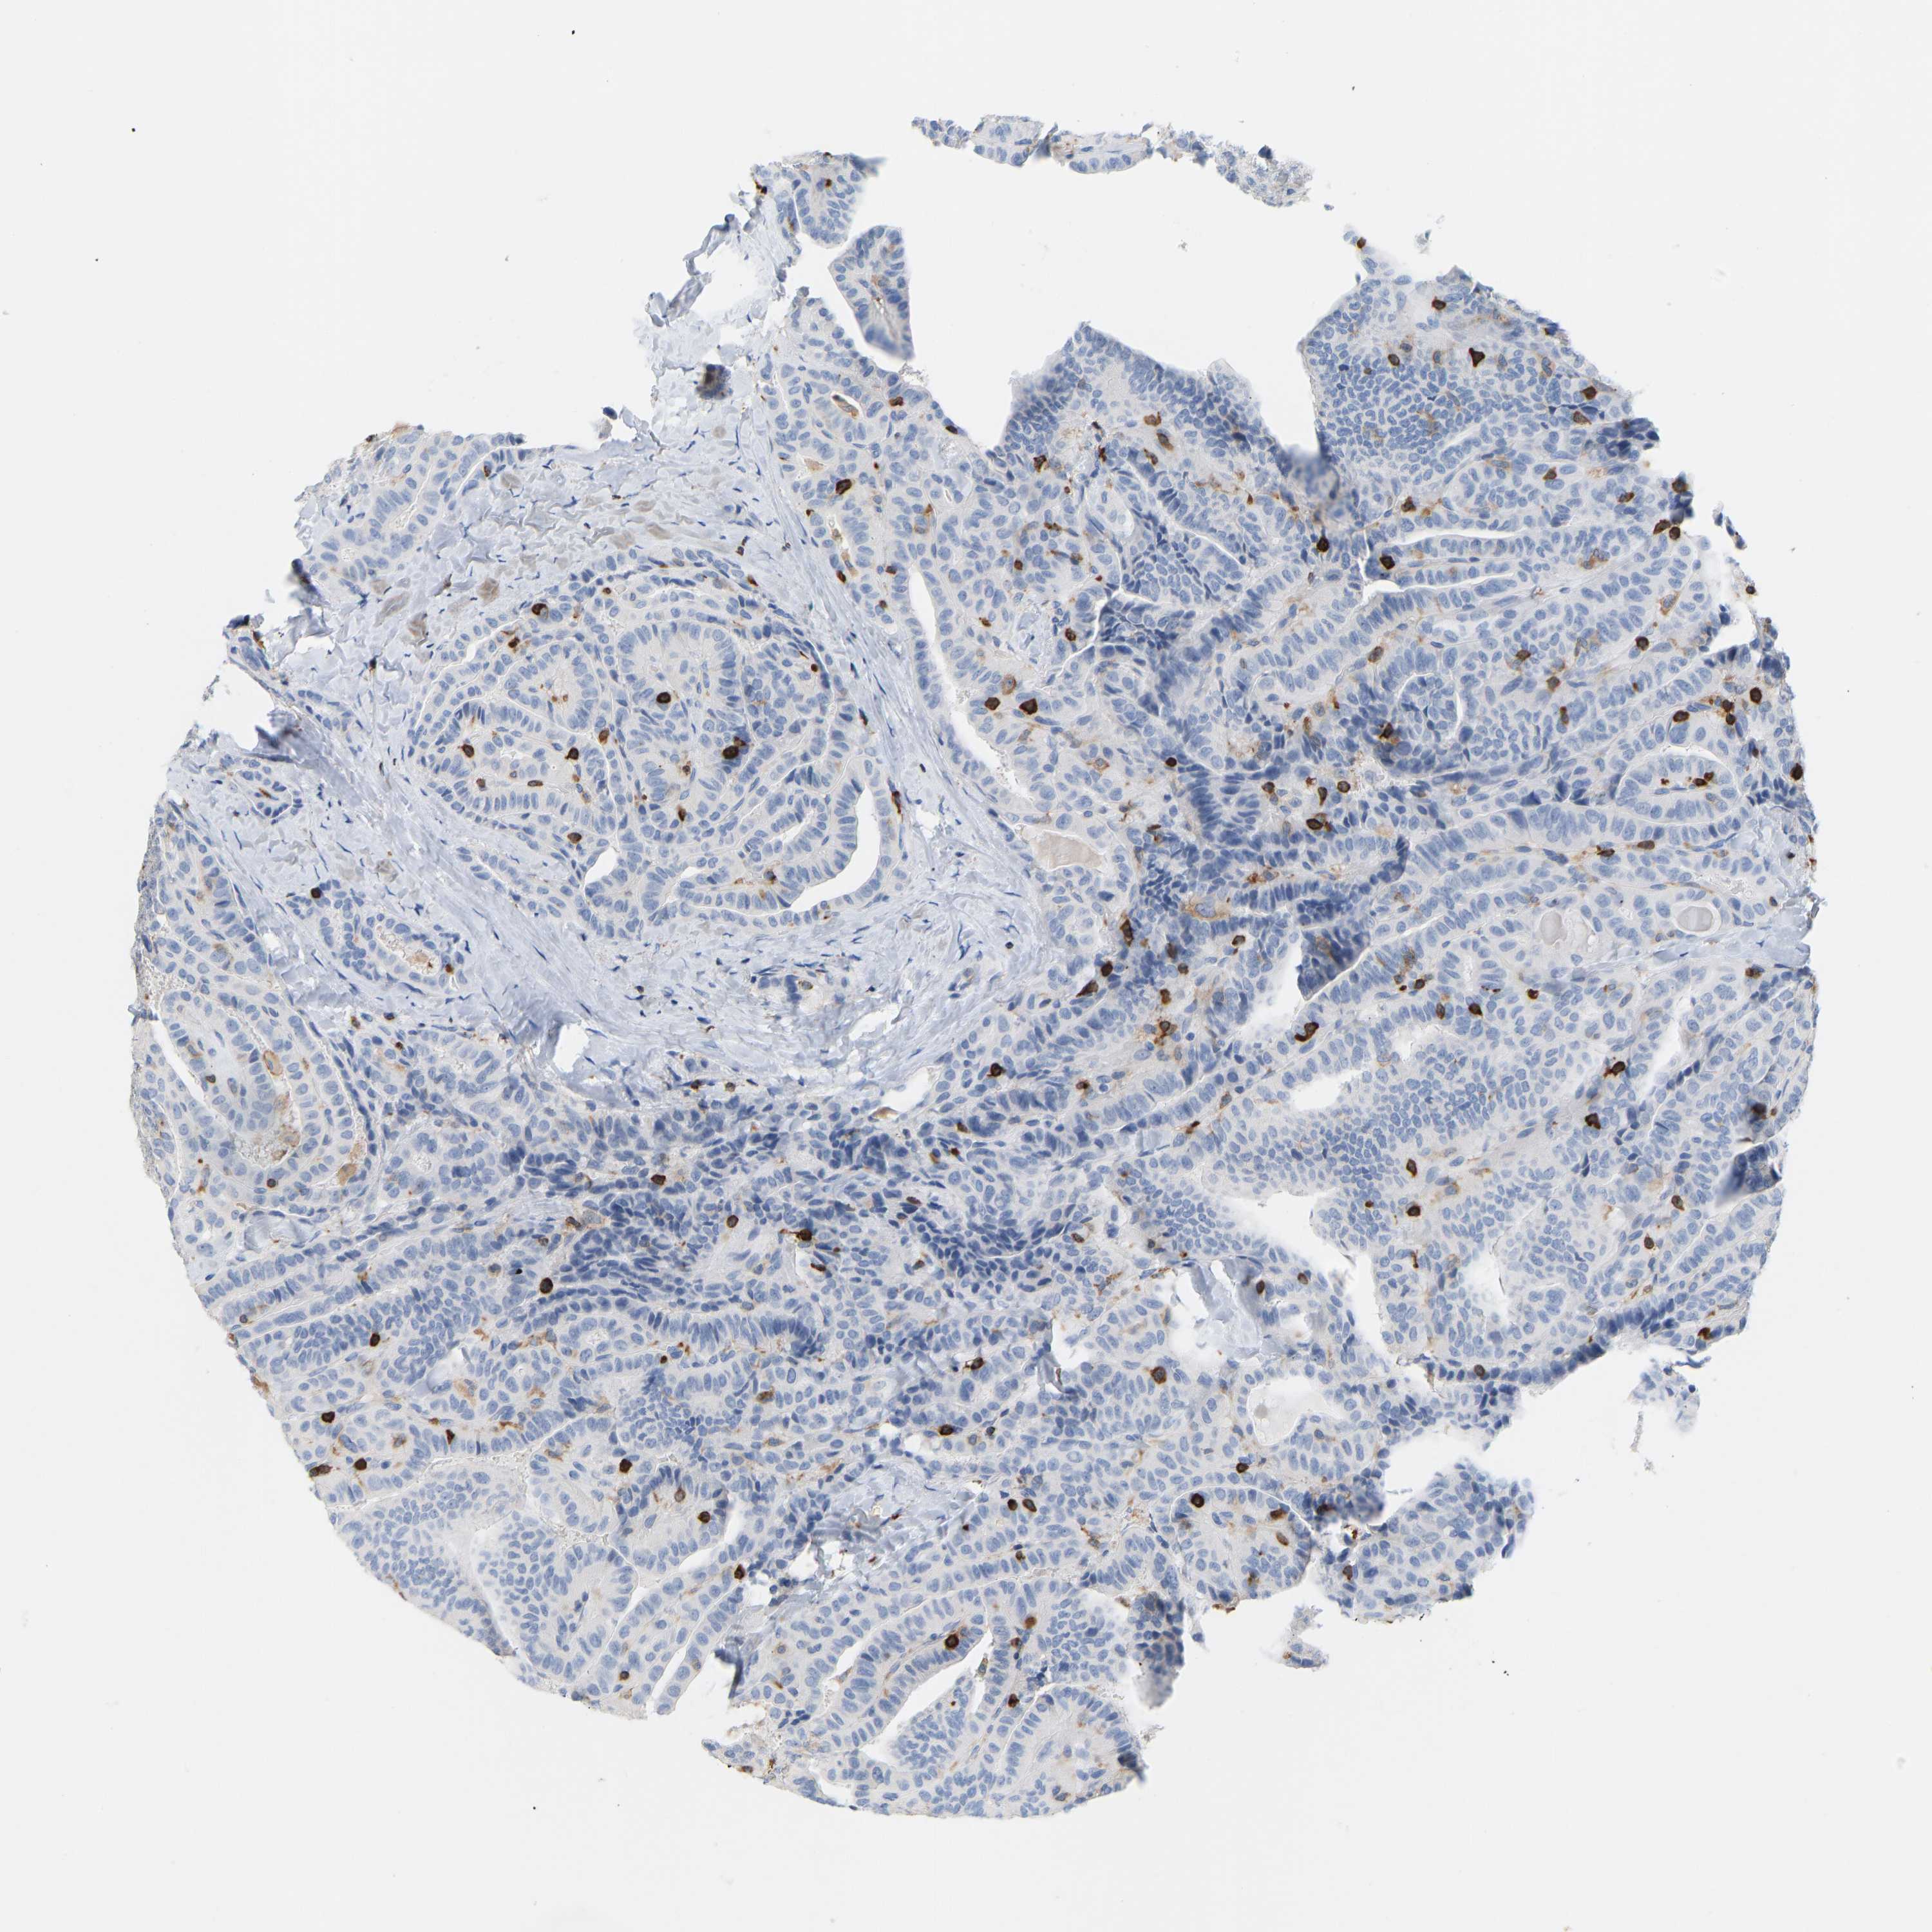

THYROID CANCER - Protein expressioni

A mouse-over function shows sample information and annotation data. Click on an image to view it in a full screen mode. Samples can be filtered based on level of antibody staining by selecting one or several of the following categories: high, medium, low and not detected. The assay and annotation is described here.

Note that samples used for immunohistochemistry by the Human Protein Atlas do not correspond to samples in the TCGA dataset.

Antibody stainingi

Antibody staining in the annotated cell types in the current human tissue is reported as not detected, low, medium, or high, based on conventional immunohistochemistry profiling in selected tissues. This score is based on the combination of the staining intensity and fraction of stained cells.

Each image is clickable and will lead to virtual microscopy that enables deeper exploration of all samples and also displays staining intensity scores, fraction scores and subcellular localization as well as patient and tissue information for each sample.

Antibody HPA018849

Antibody HPA019536

Antibody CAB033987

Staining

High

Medium

Low

Not detected

Intensity

Strong

Moderate

Weak

Negative

Quantity

>75%

75%-25%

<25%

None

Location

Nuclear

Cytoplasmic/membranous

Cytoplasmic/membranous,nuclear

Papillary adenocarcinoma, NOS

Follicular adenoma carcinoma, NOS